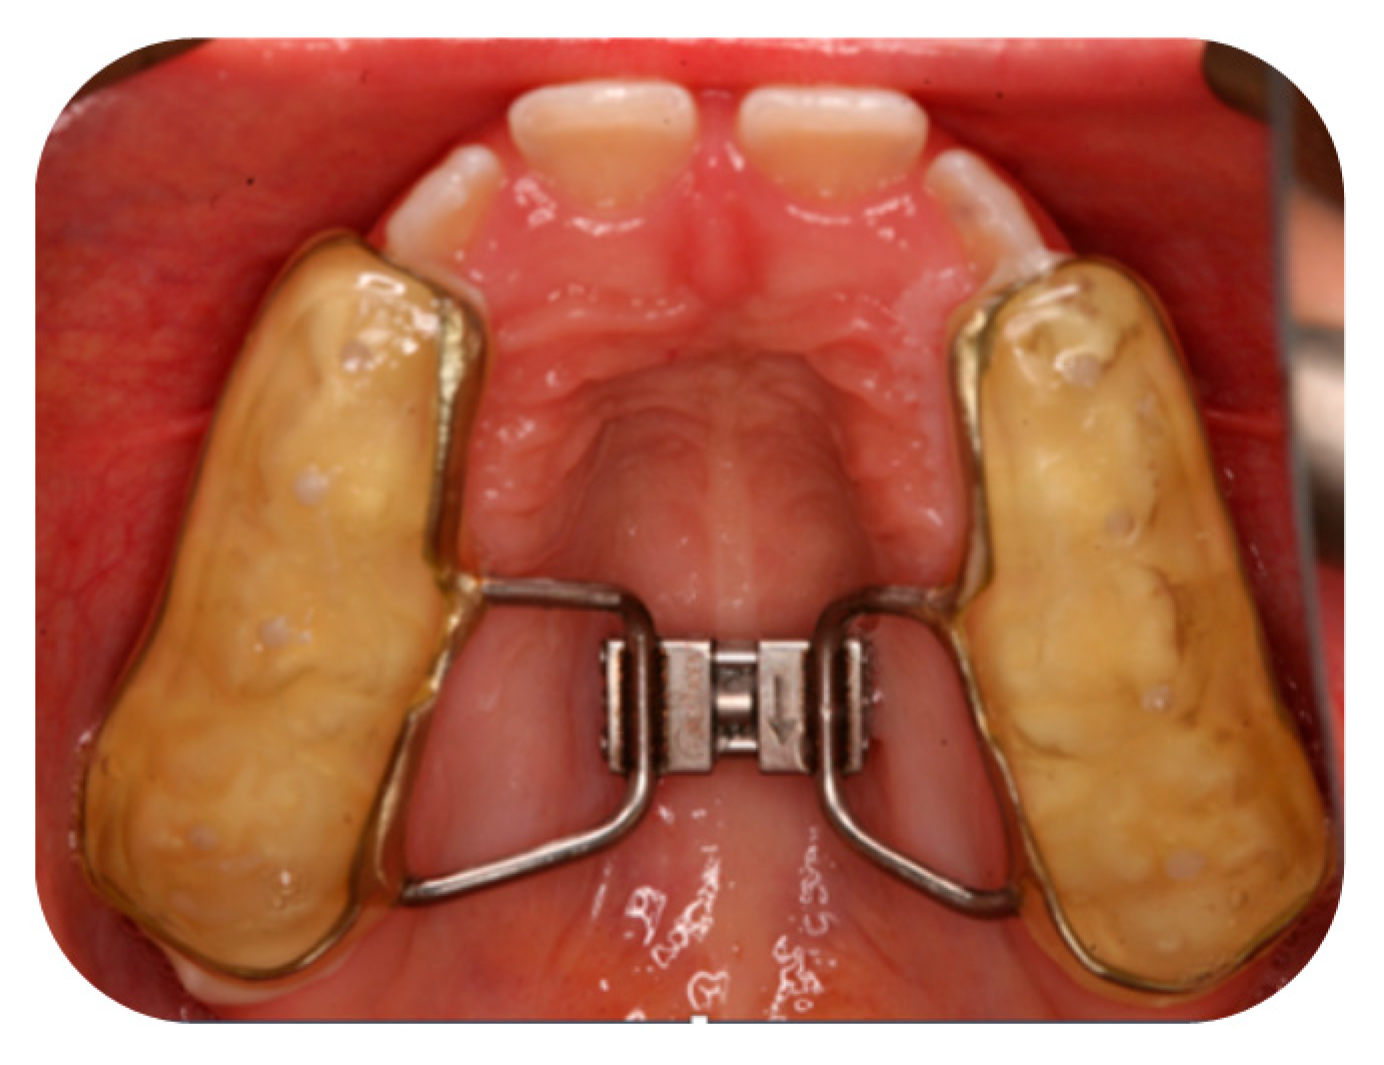

2.3. Orthodontic Treatment with RPE for Group A

Appendix A.1. Orthodontic Treatment with RPE for Group A